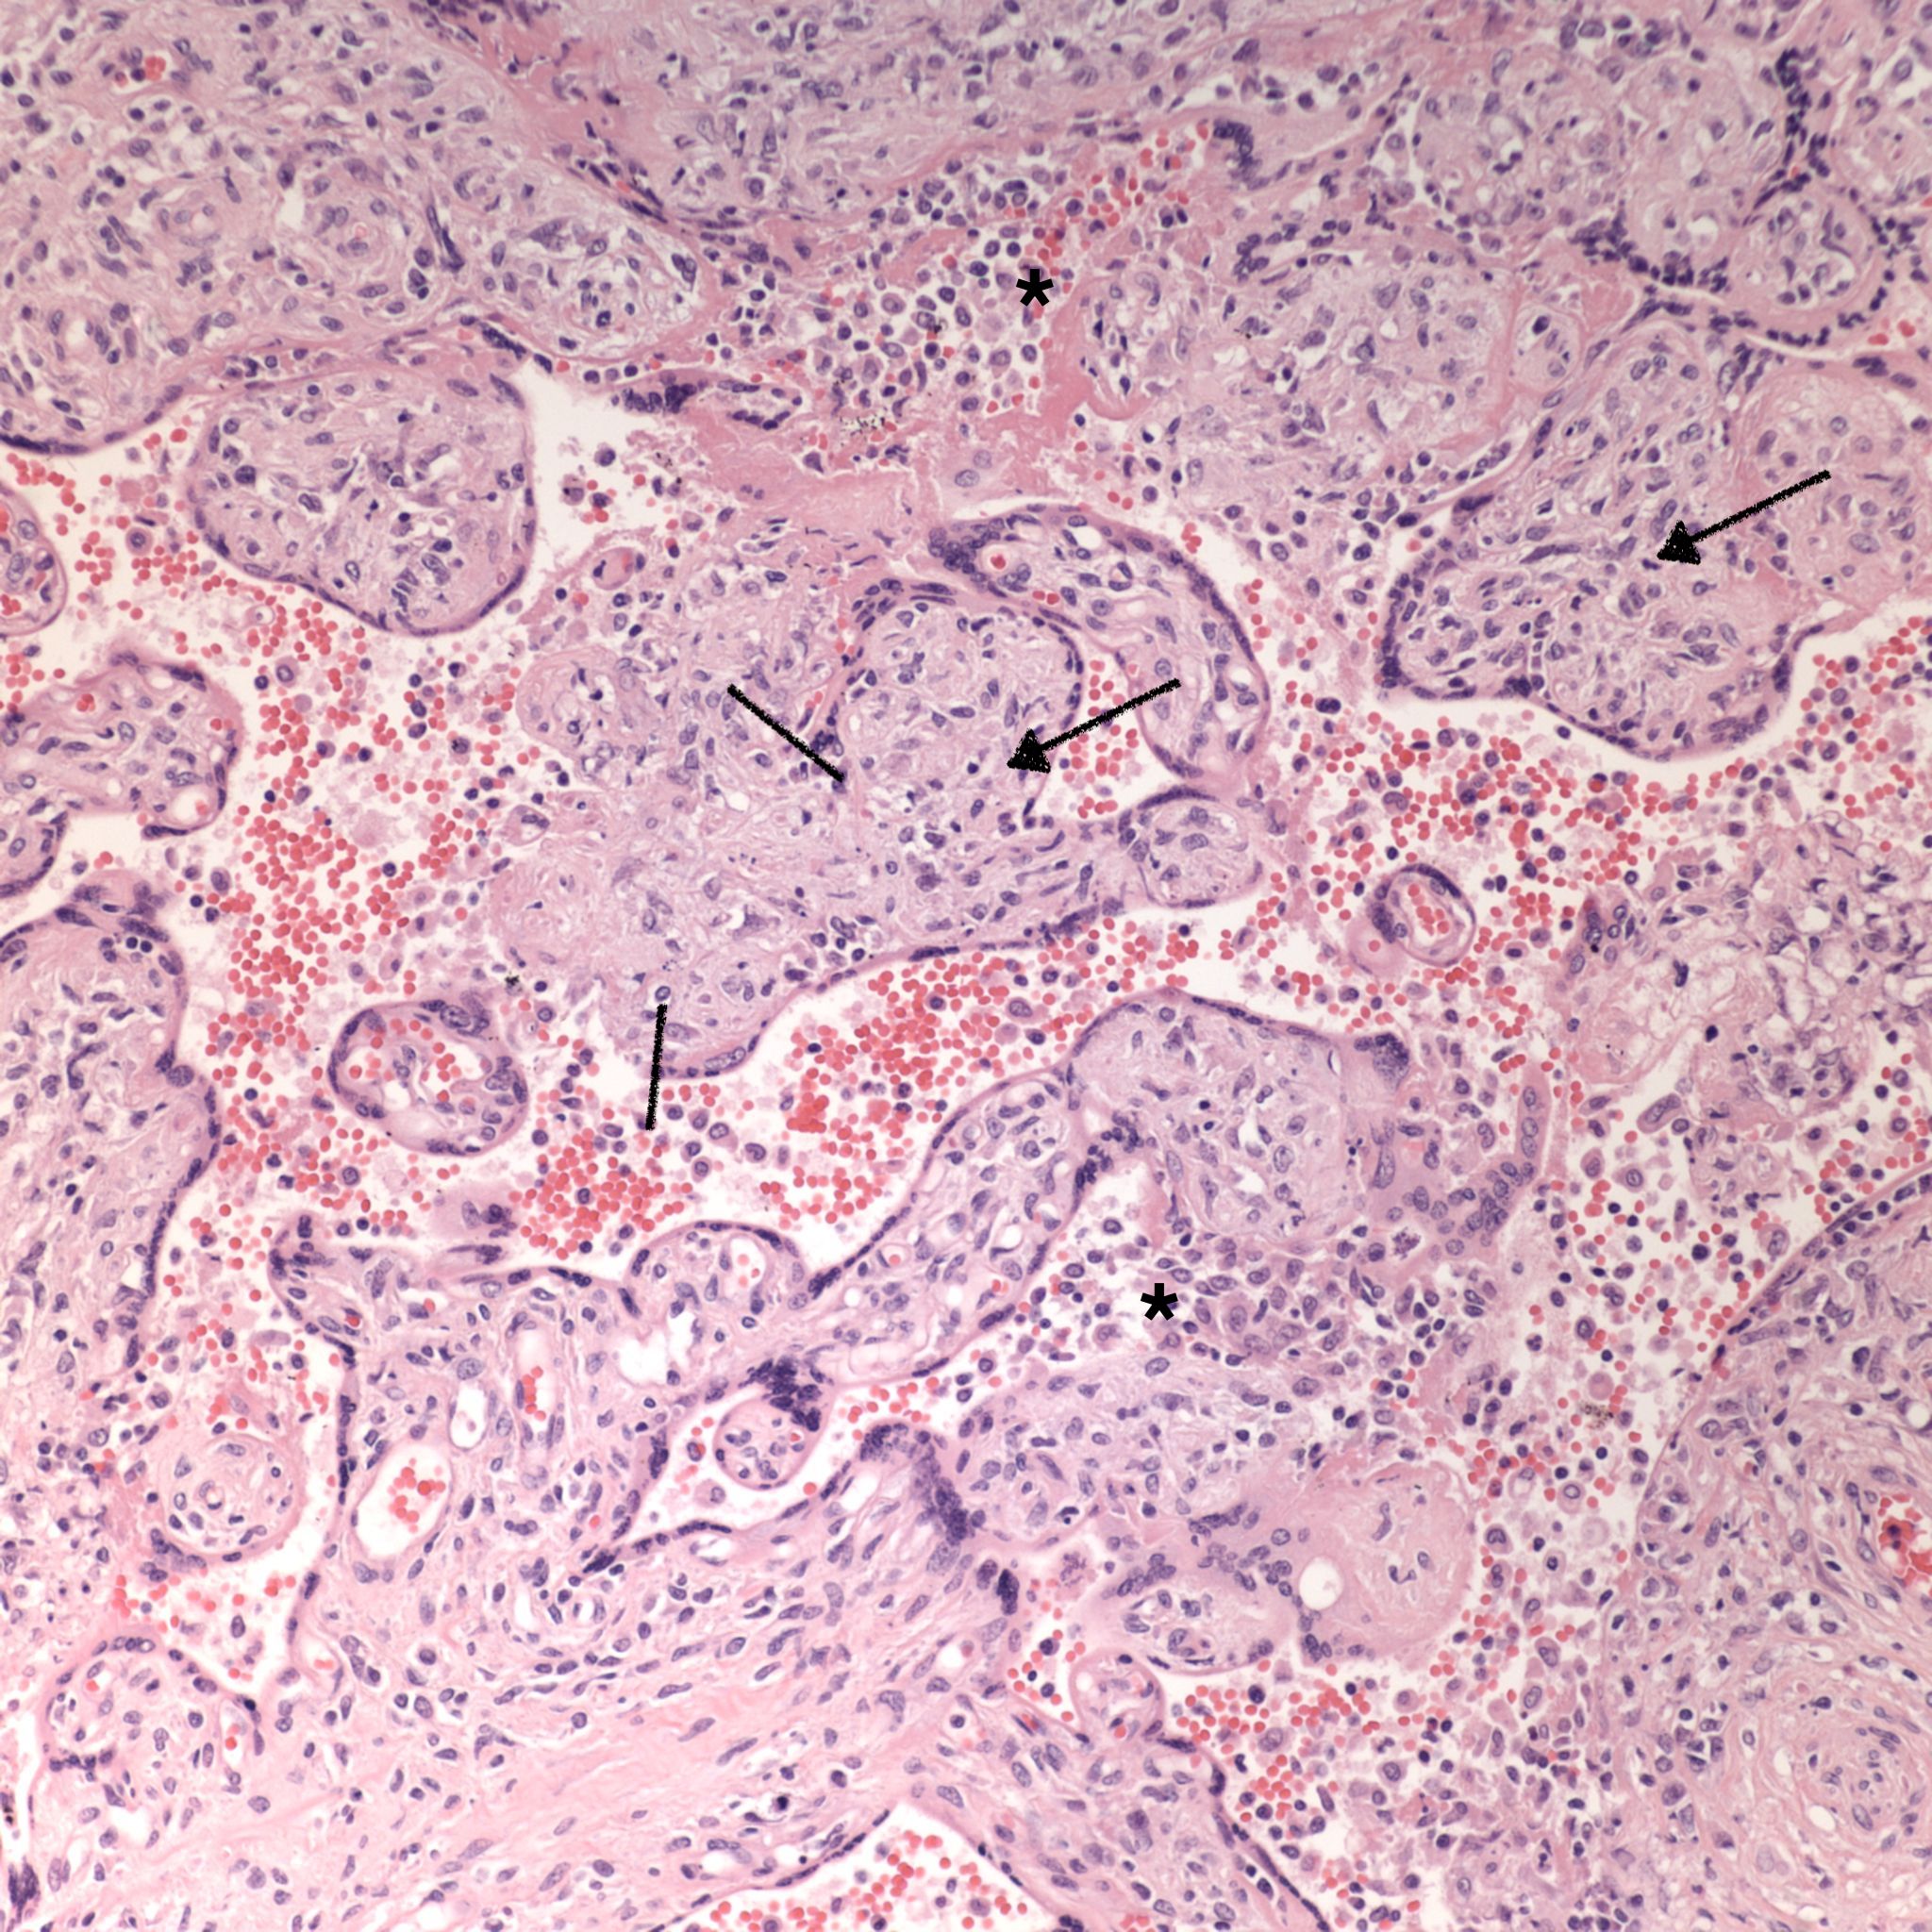

Low Grade CHIV (5-50% of the intervillous space occupied by monocytes)

There is a focus of intervillous fibrinoid with no definite cytotrophoblast that is not re-covered with syncytium suggestive of recent syncytial injury (F). (10x, H&E)

Microscopic criteria: The primary criterion is monocytes clustered in the intervillous space which can be confirmed by CD 6810,17. The monocytes often have kidney bean shaped nuclei and prominent cytoplasm. Some other consensus criteria are that the inflammatory cells in the intervillous space should be at least 80% monocytes, and these should be maternal cells1,17.

Extent and Severity: If this is an untreated case, one accepted criterion is that the monocytes occupy 5% of the sampled intervillous space. The severity can also be graded usually as less than versus more than 50% of the intervillous space filled with monocytes. The number of monocytes in the largest clusters, and whether the distribution is evenly distributed or focal may also be useful observations.